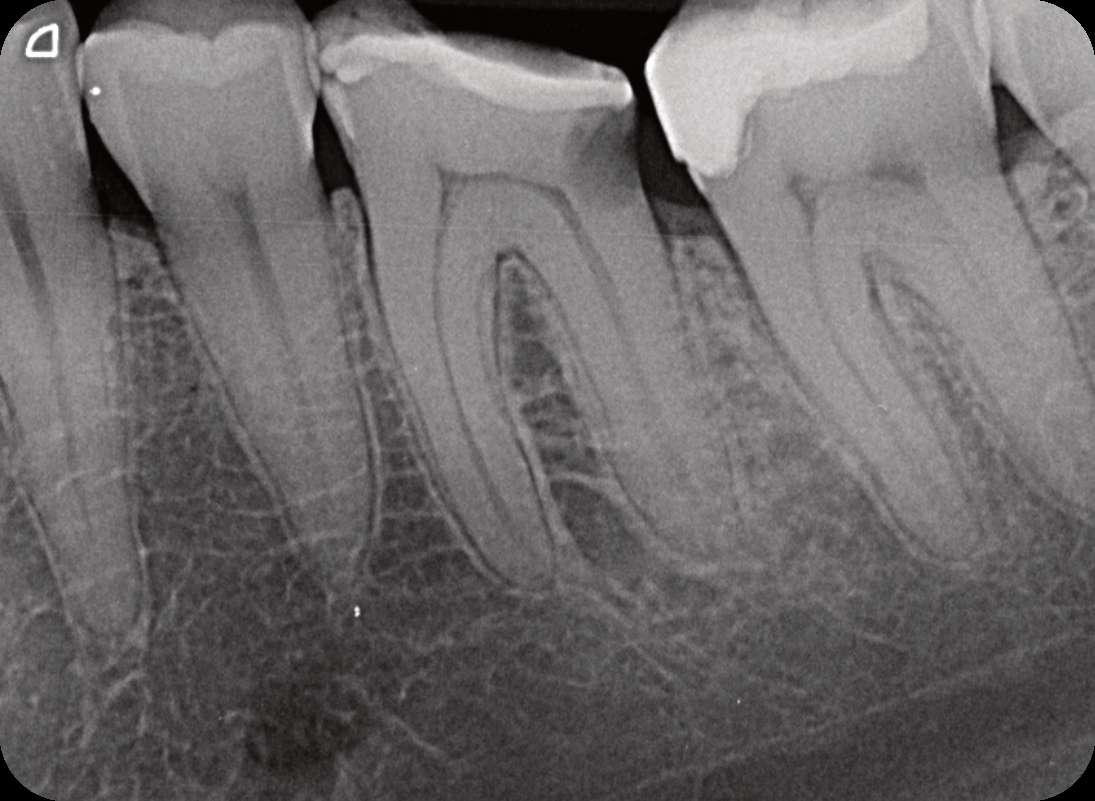

Röntgenologischer Befund: Therapie

Das präoperativ angefertigte diagnostische Röntgenbild zeigt eine insuffiziente Amalgamfüllung im distalen Approximalraum. Die mesiale Wurzel weist eine periapikale Osteolyse auf (Abbildung 1).

Abbildung 1: Präoperative Diagnostische Aufnahme

Abbildung 2: Blick auf das mesiale Kanalsystem nach Präparation

Abbildung 3: Ansicht nach Obturation Abbildung 4: Masterpointaufnahme Abbildung 5: Nach Wurzelfüllung und adhäsivem Verschluss